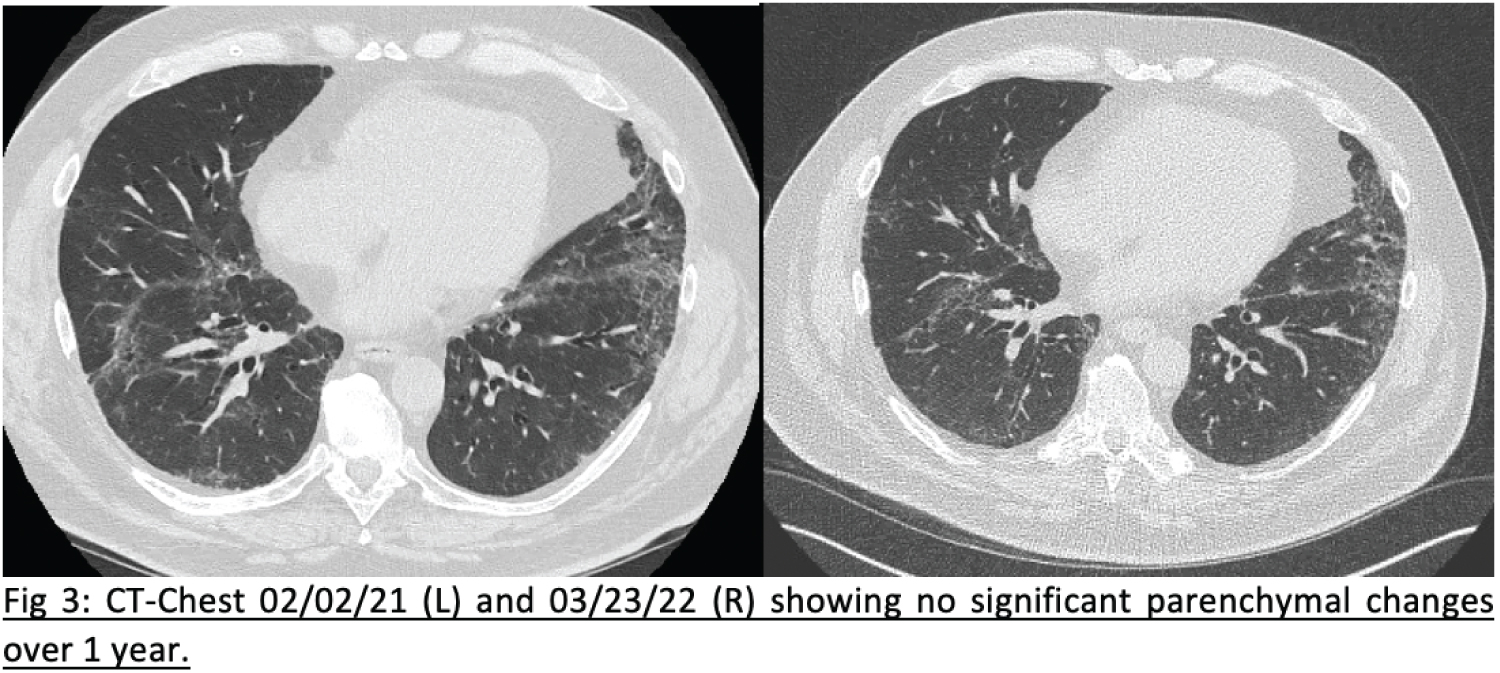

Axial images from a repeat CT in March 2022 are shown below, and show no progression in airspace disease. He has no current complaints of dyspnea or cough, and is able to do his daily activities and work without respiratory issues. There have been no hospital admissions or infections over this period. He has not had any known reported side-effects due to the IVIg transfusions (Figure 3).

Figure 3: These are 2 cropped images of cuts at a similar location, from two 0.75 mm cut high-resolution CT-chest scans, separated by 13 months. View Figure 3